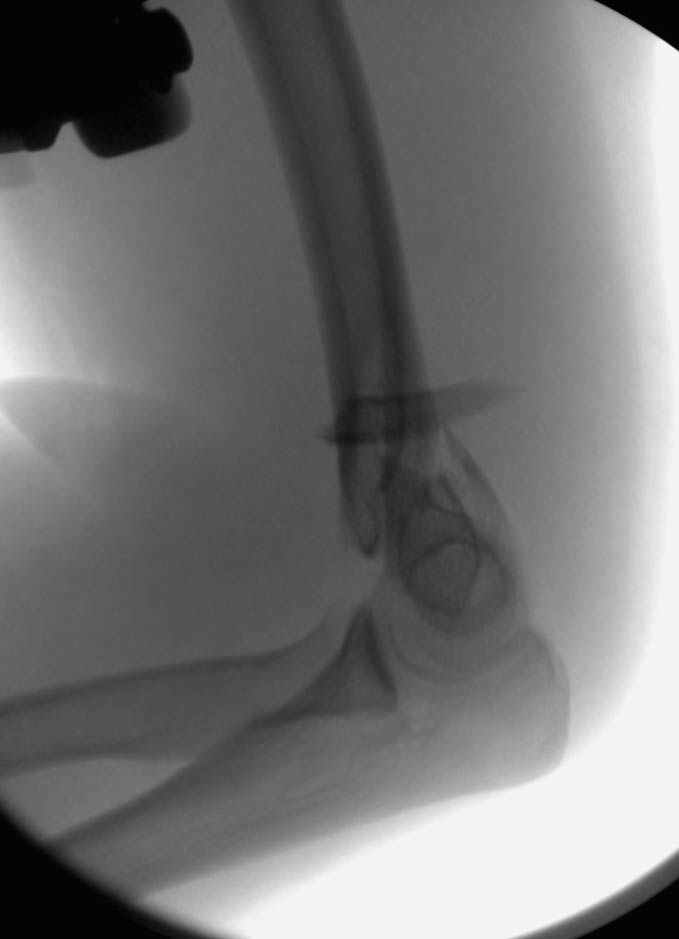

Солидарен с мнением обоих Александров (Челнокова и Рыкова): точную репозицию такого перелома вряд ли удастся выполнить закрыто. Даже во время открытого вмешательства это сделать непросто. Неслучайно предложен костно-пластический доступ с временным отсечением локтевого отростка. И по методу фиксации согласен с Александром Челноковым: 2 пластины. В качестве примера привожу рентгенограммы одного из наших пациентов с аналогичным повреждением.

С уважением, А. Золотов, Приморский край.